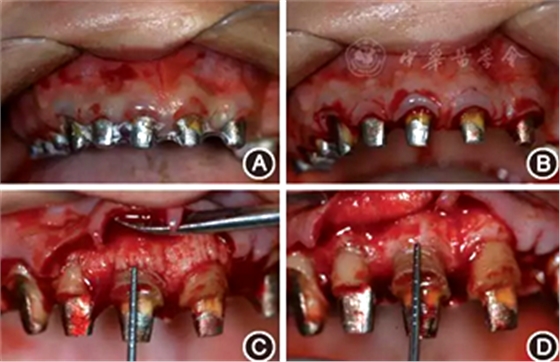

(2)手術(shù)導(dǎo)板指導(dǎo)下的牙冠延長(zhǎng)術(shù):根據(jù)最終診斷蠟型,制作透明墊式手術(shù)導(dǎo)板(圖4B),指導(dǎo)上頜牙冠延長(zhǎng)術(shù)(圖5),最終達(dá)到改善牙齦形、線、點(diǎn)的美學(xué)要求,獲得協(xié)調(diào)、對(duì)稱的美學(xué)效果。

圖5 有利于健康、功能及美學(xué)效果的牙冠延長(zhǎng)術(shù)手術(shù)過程 A:戴入手術(shù)導(dǎo)板;B:在手術(shù)導(dǎo)板的指導(dǎo)下確定手術(shù)切口;C:翻瓣后可見唇側(cè)骨板肥厚、形態(tài)不佳,上前牙鄰面及唇側(cè)原有肩臺(tái)距離骨嵴頂≤ 2 mm,侵犯了生物學(xué)寬度;D:骨切除及骨成形后唇側(cè)骨板形態(tài),肩臺(tái)距牙槽嵴頂約4 mm;E:齦瓣復(fù)位縫合,原有肩臺(tái)均位于齦上